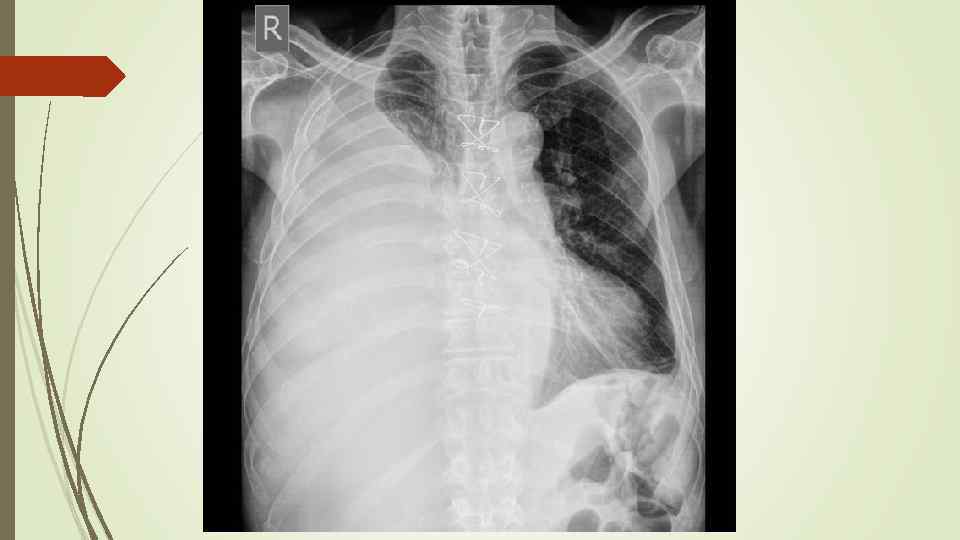

Плевральный выпот Скопление жидкости в плевральной полости (исключение гемоторакс, хилоторакс, пиоторакс) Транссудат Экссудат Плеврит

Плевральный выпот Скопление жидкости в плевральной полости (исключение гемоторакс, хилоторакс, пиоторакс) Транссудат Экссудат Плеврит

Осумкованные плевриты: а) пристеночные (паракостальные) осумкования, прилежащие широким основанием к поверхности ребер; б) верхушечные (апикальные) осумкования; в) диафрагмальные (базальные) осумкования, расположенные между основанием легкого и диафрагмой; г) междолевые (интерлобарные) осумкования, расположеные между долями легких; д) парамедиастинальные осумкования, расположенные в заворотах парамедиастинальной плевры.

Осумкованные плевриты: а) пристеночные (паракостальные) осумкования, прилежащие широким основанием к поверхности ребер; б) верхушечные (апикальные) осумкования; в) диафрагмальные (базальные) осумкования, расположенные между основанием легкого и диафрагмой; г) междолевые (интерлобарные) осумкования, расположеные между долями легких; д) парамедиастинальные осумкования, расположенные в заворотах парамедиастинальной плевры.